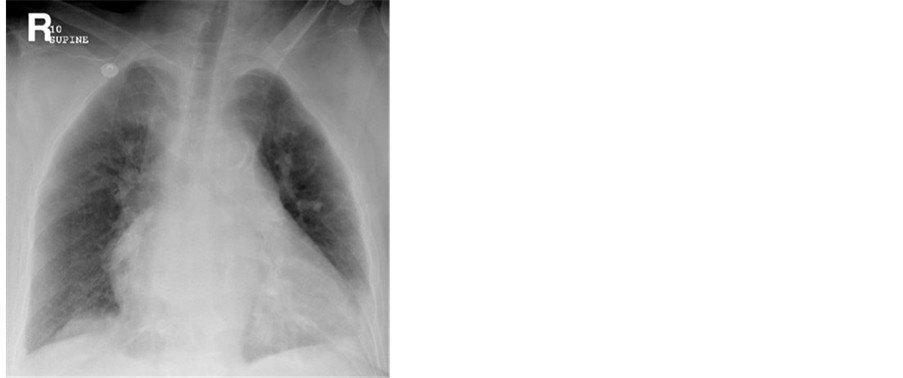

Vertebroplasty was done under local anesthesia using Acrylic Cement. The procedure was prolonged but uneventful. Upon presentation the patient denied any cough or sputum production. She did have chills and body aches. On admission, Temperature was 100.1 F. with Respiratory rate of 28 breaths per minute. On examination, she was found to have coarse breath sounds with normal cardiac vascular exam. The site of Ver- tebroplasty was intact and dry. Oxygen Saturation was 91% on 2 liter per Minute Nasal cannula. Chest x-ray upon admission was with no significant pathology (Figure 1).

Figure 1. Portable chest x-ray at presentation. Clear lungs with mild left sided pleural effusion.